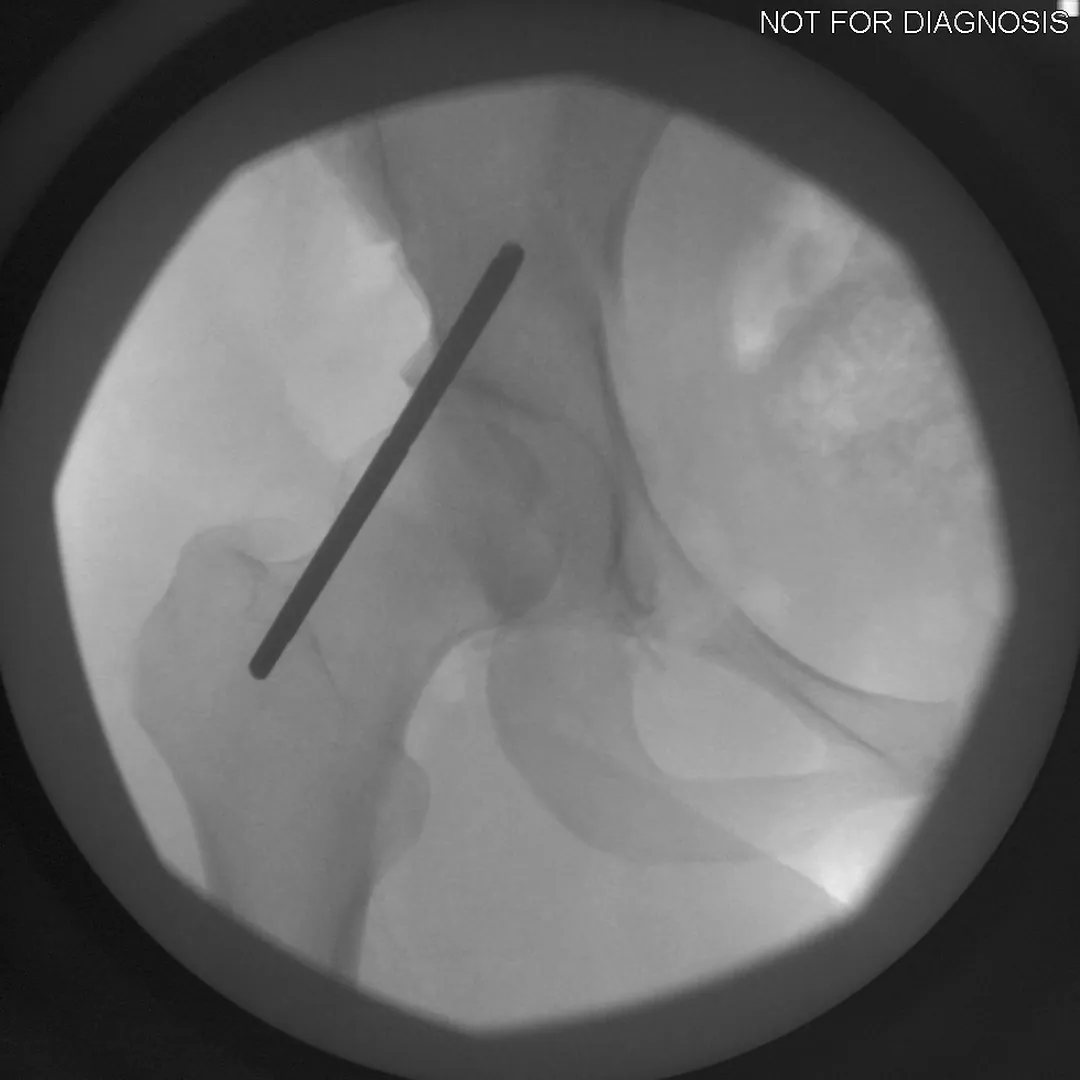

During a PAO, the surgeon carefully cuts the bone around the hip socket and repositions it to provide better coverage of the femoral head. The socket is then fixed in its new position using screws. The goal is to improve hip stability, reduce pain, and preserve the patient’s natural hip joint.

• Several controlled bone cuts are made around the hip socket

• The socket is repositioned and fixed with screws

• The hip joint itself is preserved